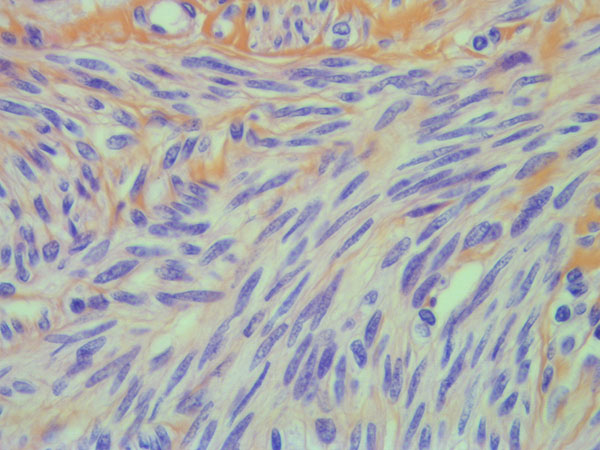

Test de dépistage du Papillomavirus Humain (HPV)

dans le cancer du col de l'utérus

L'infection par HPV est détectée dans notre cabinet par technique de biologie moléculaire en complément du frottis ou à la demande de votre soignant (gynécologue, sage femme ou médecin généraliste) en accord avec les recommandations de l'InCa et de l'HAS, selon une technique validée CE-IVD.